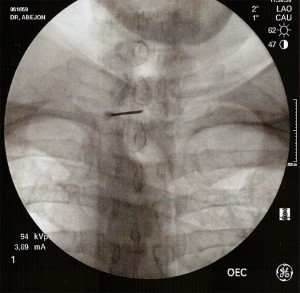

Con el paciente en decúbito prono con la cabeza en posición neutra y los brazos en dirección caudal se coloca el arco de fluoroscopia en posición anteroposterior y se localiza el espacio interlaminar seleccionado con ayuda de un marcador radiopaco. Se debe conseguir que las apófisis espinosas estén equidistantes entre los pedículos y que no exista un doble contorno en los cuerpos vertebrales. Para eliminar el doble contorno si existiera se debe de realizar u movimiento del arco de fluoroscopia en  dirección craneocaudal hasta que desaparezca. No se recomienda la punción en línea media por encima de C5 debido a la elevada incidencia de no fusión del ligamento amarillo. Una vez marcado el lugar de punción se inserta la aguja de Tuohy en visión túnel y dirección al punto diana, la entrada al espacio epidural se realiza  con la técnica de pérdida de resistencia. La técnica se puede realizar con suero, aire y gota pendiente. La elección de la técnica dependerá del entrenamiento de cada profesional con cada una de ellas. Cuando se alcanza el ligamento interespinoso, se rota el arco a posición lateral, para comprobar la profundidda de la aguja y minimizar el riesgo de punción dural. Como la visión lateral a nivel cervical es muy dificultosa por la superposición de las imágenes de los hombros, se utilizan proyecciones oblicuas y en esta posición la punta de la aguja no debe sobrepasar el borde anterior de la apófisis espinosa. Una vez localizado el espacio epidural se inyecta de 1-3ml de contraste radiopaco en tiempo real verificando la posición de la aguja y asegurándonos de que no nos encontramos en el interior de un vaso. Comprobamos nuevamente la distribución del contraste con el arco en posición anteroposterior visualizando el epidurograma y administramos un corticoide no particulado con el anestésico local. Finalmente se retira la aguja con el mandril.